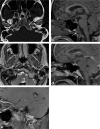

Calvarial lesions are often asymptomatic and are usually discovered incidentally during computed tomography or magnetic resonance imaging of the brain. Calvarial lesions can be benign or malignant. Although the majority of skull lesions are benign, it is important to be familiar with their imaging characteristics and to recognise those with malignant features where more aggressive management is needed. Clinical information such as the age of the patient, as well as the patient's history is fundamental in making the correct diagnosis. In this article, we will review the imaging features of both common and uncommon calvarial lesions, as well as mimics of these lesions found in clinical practice. TEACHING POINTS: • Skull lesions are usually discovered incidentally; they can be benign or malignant. • Metastases are the most frequent cause of skull lesions. • Metastatic lesions are most commonly due to breast cancer in adults and neuroblastoma in children. • Multiple myeloma presents as the classic "punched out" lytic lesions on radiographs. • Eosinophilic granuloma is an osteolytic lesion with bevelled edges.